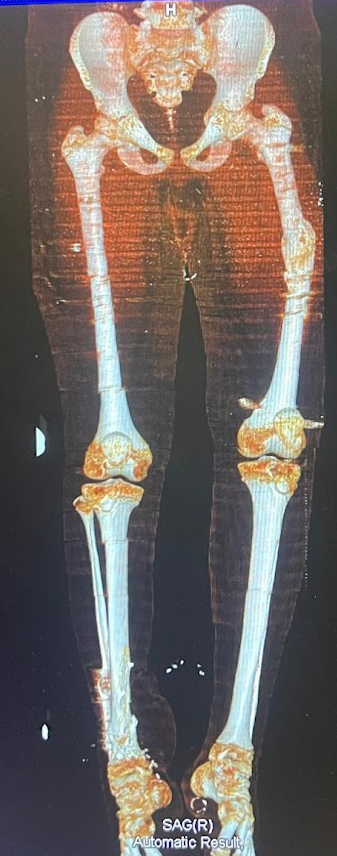

Travma ve Kırık Cerrahisi

Travma ve kırık cerrahisinde doğru planlama ve deneyim tedavinin başarısı için çok önemlidir. Cerrahisiz veya alternatif yöntemlerle tedavi mümkün olduğu düşüncesi, hastaları son yıllarda yanlış kararlara yönlendirmektedir. Her kırık kaynasa da doğru açıda kaynaması, ekleminizi sağlıklı kullanabilmeniz için hayati önem taşır.

Travma Sonrası Kırık Cerrahisi

Travmalar, günlük yaşamda en sık karşılaşılan acil durumlardan biridir. Trafik kazaları, yüksekten düşmeler, spor yaralanmaları veya iş kazaları sonucu oluşan kırıklar, hızlı ve doğru müdahale edilmediğinde kalıcı sakatlıklara yol açabilir....